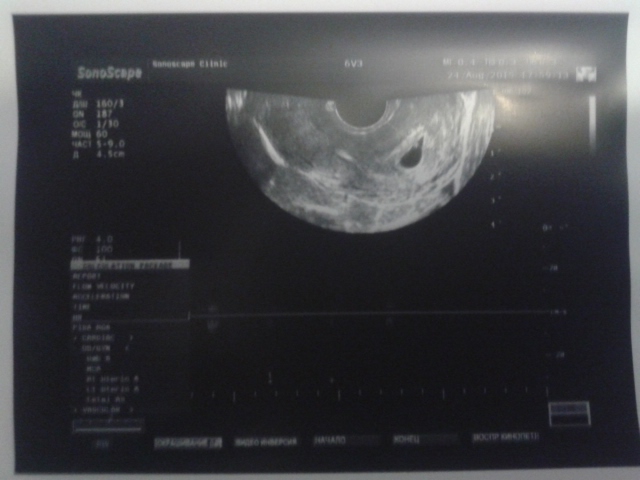

Наши будни, наши неделькиПосле моих страхов перед ЗБ, маленьким ВДПЯ (не по сроку) и низким ростом ХГЧ (45% за 48 часов) решили мы с любимым сходить на платное УЗИ, было это в минувший понедельник. И увидела УЗИстка наш эмбриончик! Значит сердечко бьётся 102-104 уд/мин, КТР 2,4 мм, срок на тот момент по УЗИ 5,5 нед (а по гестации на тот момент 6,1).